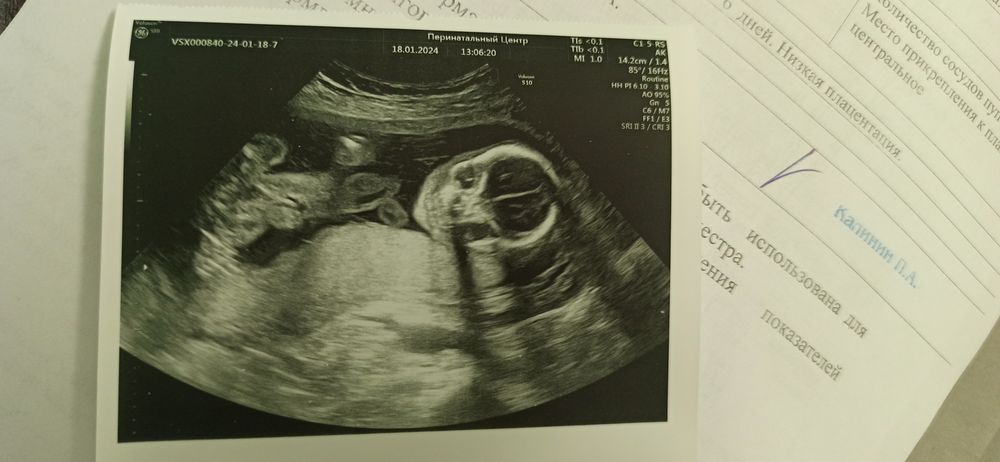

2 скрининг)

Пол малышаСегодня 21 неделя, был второй скрининг. Буквально 3 недели назад был экстренное УЗИ, узист сказал парень как и на 1 скрининге, прям 100%... А сегодня, обманул говорит... Девчонка)) я конечно радостная до капец как)) но... Будет ходить в парнячей расцветке до месяцев 7-8))) Сделали фотку личиком)

Был Дамир, стала Мирослава))

18.01.2024